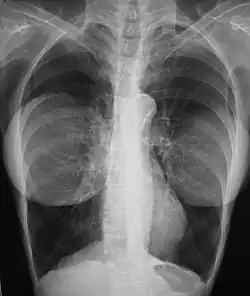

Chest X-ray showing breast implants

In the 1990s, the national health ministries of the listed countries reviewed the pertinent studies for causal links among silicone-gel breast implants and systemic and diagnosed autoimmune diseases and breast cancer.[74][38][75]  A study by researchers at the U.S. National Institute of Health reported an increase in four types of cancer among women with breast implants compared to other plastic surgery patients of the same age and similar demographic traits and health habits.[17] This increase in cancer was attenuated but did not disappear when the researchers followed the women for 5 more years, with a 43% increase in brain cancer and a 63% increase in respiratory cancer compared to other plastic surgery patients.[76]  A study by Watad et al. evaluated the medical records of more than 24,000 women with breast implants compared to more than 98,000 women with the same demographic traits who did not have breast implants. The researchers found a statistically significant 22 percent increase in several diagnosed diseases, increasing to more than 60% for Sjogren's syndrome, multiple sclerosis, and sarcoidosis[31] After investigating this issue, in 2021 the U.S. FDA revised its "black box warnings" on breast implants to acknowledge the association between breast implants and systemic autoimmune, rheumatologic, and neurological symptoms to state: "Patients receiving breast implants have reported a variety of systemic symptoms, such as joint pain, muscle aches, confusion, chronic fatigue, autoimmune diseases, and others. Individual patient risk for developing these symptoms has not been well established. Some patients report complete resolution of symptoms when the implants are removed without replacement".[77]